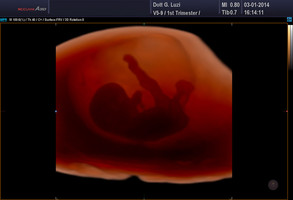

Gravidanza

Dottor Giuseppe Luzi accompagna la vostra gravidanza passo per passo, dall'assistenza prenatale al momento del parto, dalle ecografie alle analisi di laboratorio, alla cardiotocografia che vi permette di sentire i battiti del cuore del feti

il Dottor Luzi desidera che viviate la vostra gravidanza con serenità e felicità. Per questo vi fornisce una consulenza approfondita e mette a vostra disposizione tutta la sua esperienza.